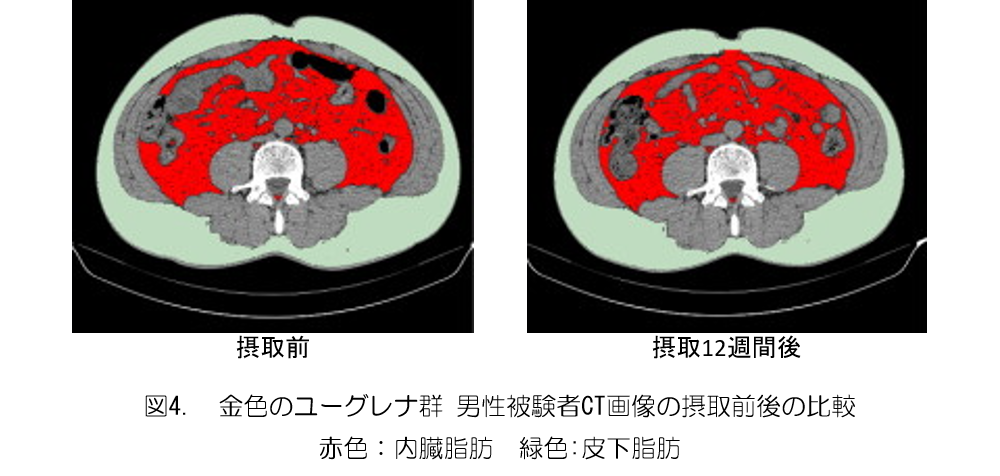

男性の比較においては、金色のユーグレナ群は対照群と比較して、内臓脂肪面積の有意な低下が確認された(図3、4)。